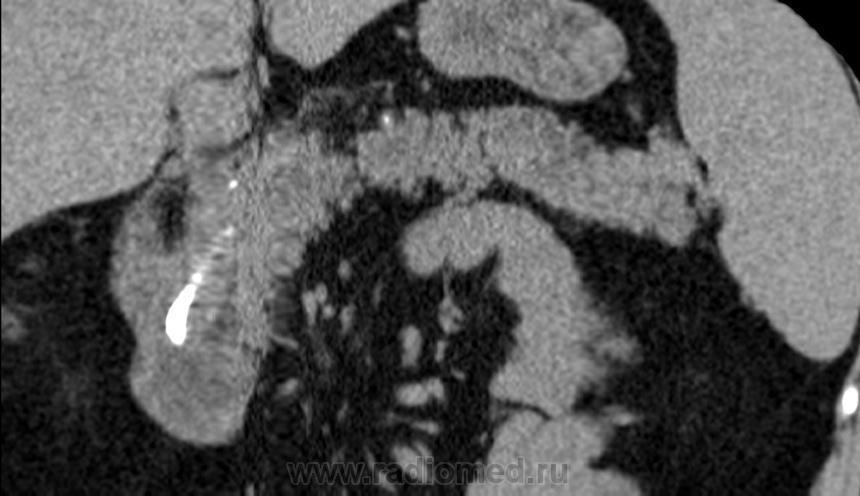

Итак пациент мужчина 34 года, в анамнезе - 16 эпизодов острого панкреатита (!). Пациенту была выполнена ЭРХПГ которая выявила наличие двух стриктур протока Вирсунга в области головки поджелудочной железы (доброкачественная стриктура Вирсунгова протока). На представленных мной изображениях определяется неоднородная структура поджелудочной железы с гиподенсными участками в области тела/хвоста и наличием паренхиматозных кальцификатов (b & c). Такая картина указывает на хронический панкреатит. В области головки визуализируется стент (a), установленный в Вирсунгов проток, с свободным концом в просвете 12-ти перстной кишки. Такое стояние стента является правильным. На данный момент, единственной адекватной терапией при доброкачественных стриктурах протока поджелудочной железы (и при некоторых опухолях исходящим из протока или обтурирующих его, когда невозможно выполнить резекцию) является эндоскопическое стентирование протока, что обеспечивает нормальный отток секрета поджелудочной в кишечник.

Верно. Об обструкции стента можно заподозрить только при наличии расширения протока дистальнее, или если пациент поступит с новым приступом острого панкреатита. В профилактических целях, стент периодически меняют.

Дело не в окне. Оболочка стента из полимера, структура стента включает в себя рентгенконтрастные молекулы различных металлов (хим. соединений из группы металлов). Т.е. сам стент не из "железа".